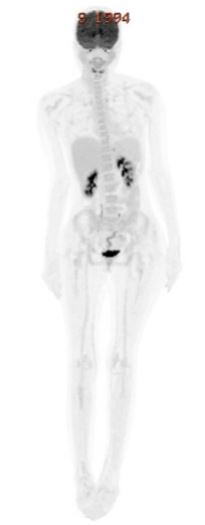

At day 28 evaluation, the bone marrow was hypocellular (10–20%) with 2% blasts. Minimal Residual Disease (MRD) analysis detected 0.7% residual myeloid population (CD117+, CD13+, CD33+, CD34^dim, HLA-DR+, CD15+, CD38+), while no T-lymphoblasts were identified. PET-CT demonstrated an excellent metabolic response with residual low-level uptake in bilateral cervical lymph nodes. Owing to persistent MRD and extramedullary activity, consolidation with Hyper-CVAD Part B ( High-dose Methotrexate and Cytarabine (Ara-C)) was administered in July 2025, together with continuation of venetoclax (Table 2). Repeat marrow examination demonstrated normocellularity (70–80%) with trilineage hematopoiesis and no morphologic or immunophenotypic evidence of disease; MRD was negative at the 0.01% threshold. Repeat PET scan showed complete metabolic resolution of prior (Figure 3).

Figure 3: PET-CT post HYPER-CVAD B + venetocloax demonstrated an excellent metabolic response with residual low-level uptake in bilateral cervical lymph nodes.